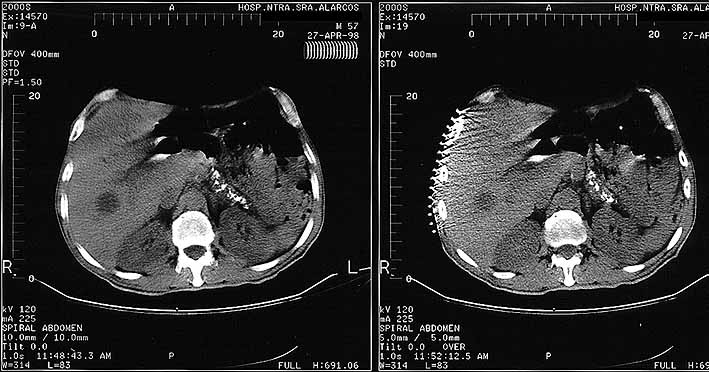

fig. 1

Figura 1. TAC LOES hepáticas

fig. 2

Figura 2. TAC Higado durante PAAF de hígado.